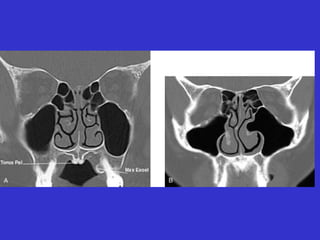

Este documento describe las diferentes proyecciones radiográficas utilizadas para examinar los senos paranasales, incluyendo las proyecciones básicas de Caldwell, Waters lateral y las proyecciones especiales como Hirtz y Waters mentonasal. También describe las diferentes estructuras anatómicas que componen el complejo ostiomeatal anterior y posterior de los senos paranasales.